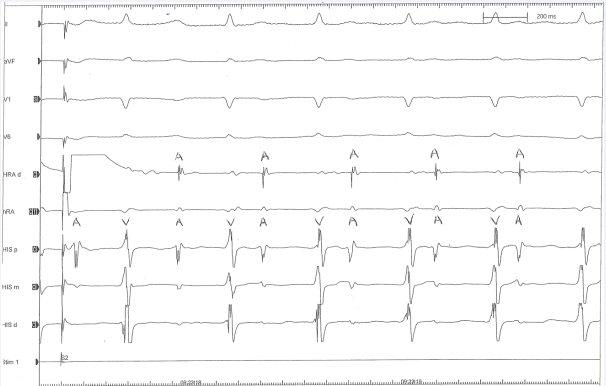

Using the nonfluoroscopic system, mapping images were created of the right atrium and its intracardiac structures, including the coronary sinus vein, the inferior and superior vena cavae, and the crista terminalis. The catheters themselves were also visualized. Using the catheters’ mapping capability, a full conduction study was performed and programmed electrical stimulation (A1A2) induced a nonsustained atrial tachycardia at a cycle length of 380 msec (Figure 2).

Figure 2: Surface and intracardiac electro grams from the electrophysiology study, which was performed solely with the use of 3D nonfluoroscopic electroanatomic mapping. The intracardiac electro grams show catheters placed in the atrium and near the His bundle which demonstrate an atrial tachycardia at a cycle length of 380 msec.